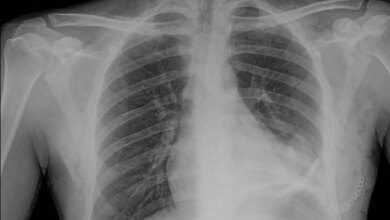

وبيّنت أن التشخيص تم باستخدام تقنيات إشعاعية وسريرية متقدمة، إلى جانب ابتكار طبي سعودي جديد يتمثل في رسم خط وهمي على الأشعة الطبقية المحورية، أُطلق عليه اسم “Bin Turayki’s Line”، تكريمًا للدكتور بن تريكي، ليسهّل عملية التشخيص في الحالات المشابهة حول العالم.